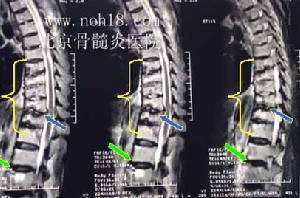

本病大部分可出現急性腹痛,神經根性痛,髖關節痛,或嚴重敗血症等症狀。在一些病例中,炎性細胞浸潤椎旁軟組織可形成椎旁膿腫,表現為受累椎體、椎間盤及相鄰椎體的椎旁軟組織增厚,橫斷面病變呈環繞椎體的軟組織腫塊影,膿腫範圍累及硬膜外間隙可致使硬膜囊腹側受壓呈弧形改變,嚴重時累及脊髓,甚至脊髓嚴重受壓變形,引起截癱。

(3)、MRI表現為椎體呈長T1、長T2異常信號,FLAIR序列及增強掃描對明確診斷有很大幫助;

椎體及附屬檔案破壞變形,呈長T1、長T2信號改變,椎體邊緣信號異常部分與正常分界模糊,椎間盤失去正常形態及信號,呈不同程度的腫脹增厚或破壞、碎裂,椎間隙有不同程度狹窄,呈長T1、更長T2改變,椎前、椎旁軟組織腫脹,T1WI上與肌肉組織相似,T2WI上信號更高,邊緣有線樣低信號影可能為膿腫壁,增強掃描後,受累椎體、間盤及寒性膿瘍的周邊有異常對比增強。臨床有結核病史及結核中毒症狀。

椎體邊緣可有增生改變,相鄰椎體邊緣T1WI呈低信號,T2WI呈高信號,椎體邊緣信號異常部分與正常部分分界清楚,附屬檔案無破壞。椎間盤變性改變:T1WI,T2WI上均呈低信號。椎旁軟組織正常;行Gd-DTPA增強掃描椎體終板及相鄰椎間盤不強化。